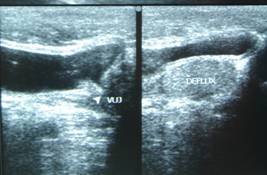

Recurrent abdominal pain is a common and vexing problem in children especially between 2 and 10 years. Abdominal pain which causes disturbance in sleep, school drop outs and hindrance in day to day activities of the child needs medical attention. It is mandatory to get the child checked up by a doctor and get an ultrasound scan done if necessary.

Ultrasound scan is a common and non invasive investigation which does not have any radiation exposure. It can pick up pathologies that are not visible on the outside or may not be apparent on clinical examination. One of the most common things that is picked up on ultrasound scan is enlarged mesenteric lymph nodes. The most common cause of this is intestinal infections or appendicitis. Rarely they can be due to tuberculosis or malignancy. In a well child, the size of these glands may be monitored by ultrasound scan on a monthly basis. If the size of the glands persist to 1.5 cm or larger and if there are multiple glands in the abdomen, a laparoscopic biopsy of the mesenteric lymph nodes may be helpful to arrive at a scientific diagnosis. ●